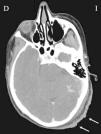

Piel. Formación continuada en dermatología Enfermedad de Kimura: una enfermedad rara en un paciente atípico

Enfermedad de Kimura: una enfermedad rara en un paciente atípico

Kimura’s disease: A rare disease in an atypical patient